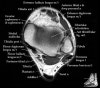

발목 관절의 MRI 단면 영상

- Coronal section

The coronal oblique T1 sequence follows the tendons of the ankle around the malleolar turns and also evaluates the medial ankle ligaments.

The coronal oblique PD fat suppressed sequence follows the tendons of the ankle around the malleolar turns and is particularly important in evaluation of the Posterior tibialis tendon.

Bone and marrow

Talar dome

Deltoid ligament

Tendons in arch

Plantar fascia

Troubleshoot ligaments